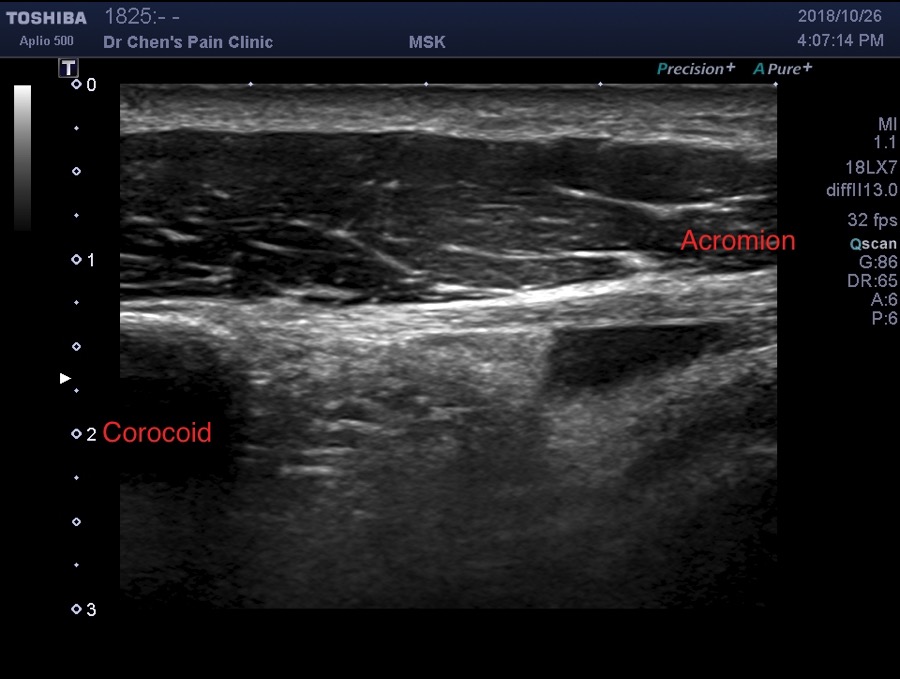

肩峰下滑液囊積水

當肩膀疼痛的患者,出現肩峰下滑液囊積水的時候,代表了什麼意思呢?